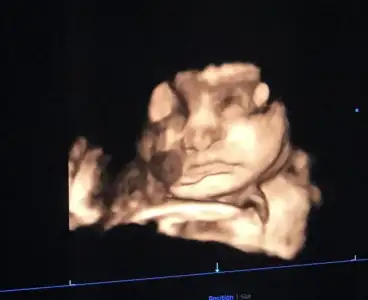

B Buffalosos D Dr X kızlar yok mu bebiş renkli ultrason fotosu teyzesi merak etti kuzuları, gostermezseniz bana bozusuruz bak🤣🤣 çok sevdim bebeklerinizi hep takip ediyorum, inşaallah ben de bir gün karnimda sağlıklı tekmeler hissederim 🤭

Yaaa olmaz mı sen istersin atmaz mıyım 30+6 dan bi foto atıyorum zorla açtık yüzünü 🤣

• 636eabaa-b383-4a4a-ae4f-6e191d0ad6c5.webp

636eabaa-b383-4a4a-ae4f-6e191d0ad6c5.webp

17,9 KB · Görüntüleme: 102